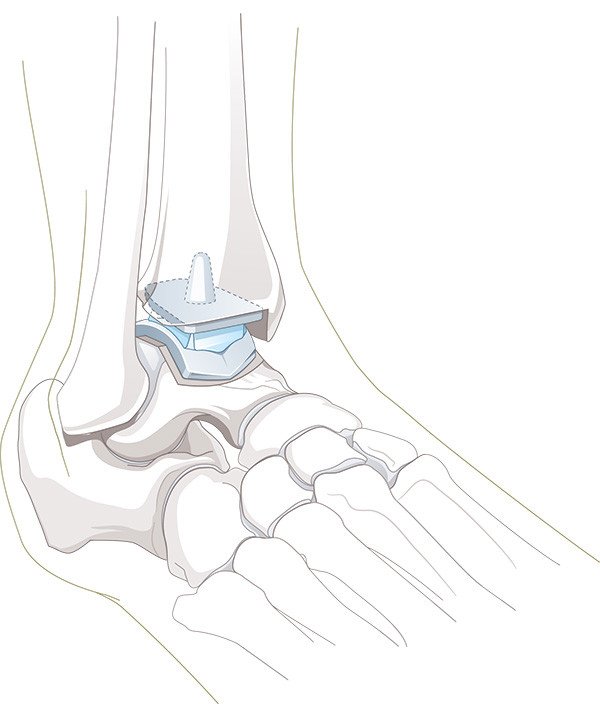

Kunstgelenk

Zur Behandlung der Arthrose an grossen Gelenken wie Hüfte, Knie, Schulter oder Ellbogen hat sich der Gelenkersatz seit Jahrzehnten etabliert. Weil es funktionell zu den grossen Gelenken zählt, wurde schon früh versucht, auch im Sprunggelenk Kunstgelenke einzusetzen. Verschiedene Gründe haben aber noch bis Mitte der 70er-Jahre fast konstant zum Versagen dieser Kunstgelenke geführt. Neuere Designüberlegungen haben schliesslich die Weiterentwicklung der Sprunggelenkprothese hervorgebracht, wie wir sie heute kennen.

Die Nachbehandlung für Patienten mit einem Kunstgelenk erfordert eine wesentlich intensivere Betreuung: Sobald es die Wundverhältnisse erlauben (in der Regel nach ca. 1 Woche), wird unter Anleitung der Physiotherapie das Gelenk mobilisiert. In dieser Phase ist zwei- bis dreimal pro Woche Physiotherapie erforderlich. Sie werden ausserdem über Übungen zur Mobilisation für zuhause instruiert.

Auch wenn in vielen Fällen eine Vollbelastung des Kunstgelenks bereits früh erlaubt werden kann, empfiehlt es sich, die Gehstöcke für ebenfalls etwa sechs Wochen zu benützen. Das Endresultat wird nach vier bis sechs Monaten erreicht, in Einzelfällen dauert die Rehabilitation bis zu einem Jahr. Mit verschiedenen manuellen Techniken werden die Weichteile behandelt und das Sprunggelenk mobilisiert. Dies fördert die rasche Wundheilung und verbessert die Beweglichkeit des neu implantierten Gelenks.